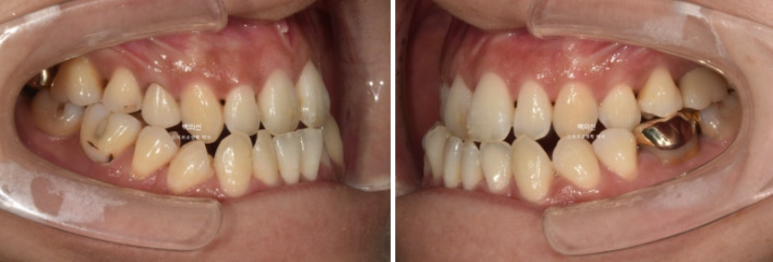

24.01~25.07

앞니 뿐만 아니라 어금니 반대교합도 함께 개선되었습니다.

중심선은 개선되었습니다.